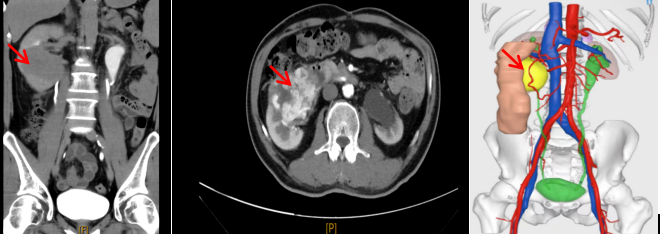

机器人辅助腹腔镜下肾癌根治术+Mayo II 级下腔静脉癌栓取出术

机器人辅助腹腔镜下肾癌根治术+Mayo II 级下腔静脉癌栓取出术肾癌合并下腔静脉癌栓手术被称为泌尿外科“皇冠上的明珠”,手术风险和难度极高,目前科室在开放肾癌根治+下腔静脉取栓手术的基础,常规实施“机器人辅助腹腔镜下肾癌根治术+Mayo II下腔静脉癌栓取出术”,近几年成功实施复杂的Ⅲ、Ⅳ级癌栓手术,荣获医院“技术创新一等奖”,成为区域复杂肾癌诊疗的典范。